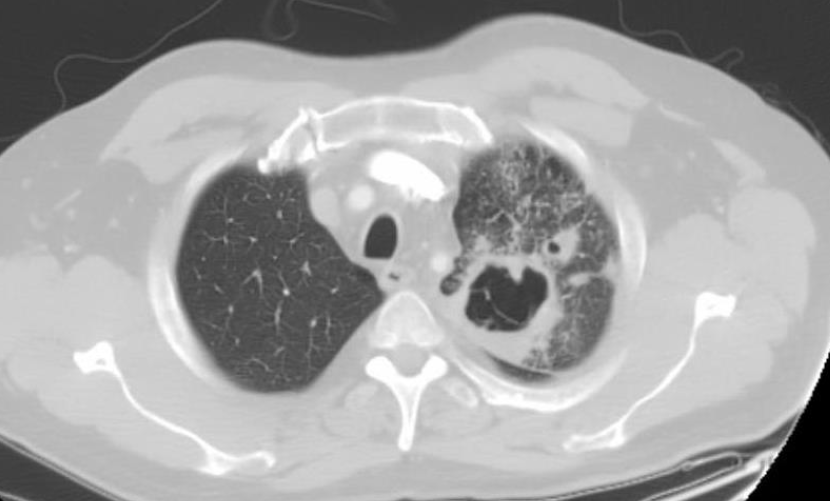

Pulmonary involvement in paracocci?

Non specific symptoms - cough,haemoptysis, SOB Bilateral infiltrates on CXR Cavitating lesions and pleural effusions - NOT COMMON

110